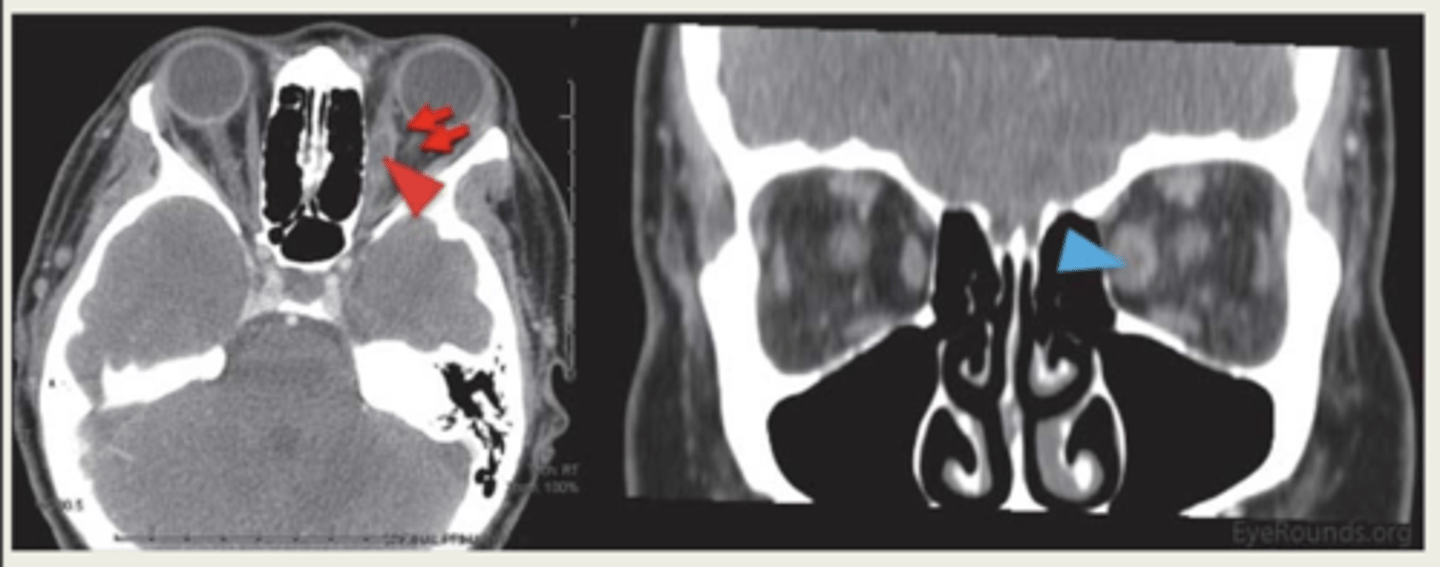

What is an intraorbital foreign body?

foreign body inside orbit but outside globe

What causes an intraorbital foreign body?

high velocity injury

What is the presentation of intraorbital foreign body?

orbital mass:

1. proptosis if mass is large

2. ptosis if mass is superior

3. restricted EOM movement if mass is near EOM

What is the workup for infraorbital foreign body?

CT scan or MRI (no metal)

What is the treatment for an intraorbital foreign body?

observe if small and deep

1. tetanus prophylaxis

2. oral abx

3. surgery